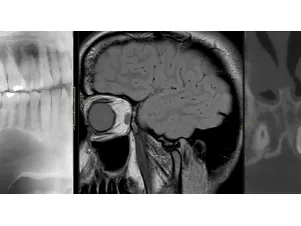

This training is accredited by EACCME with 9 CME credits The dental and maxillofacial imaging fellowship aims to develop the interpretation skills of radiologists and dental professionals in imaging of the dental and maxillofacial region.

The training will cover all essential topics related to dental and maxillofacial imaging.

Lectures will include dental and maxillofacial imaging anatomy, principles of imaging modalities relevant to dental and maxillofacial imaging and recognising imaging features of common pathologies of the dental and maxillofacial region.

Modalities: MRI